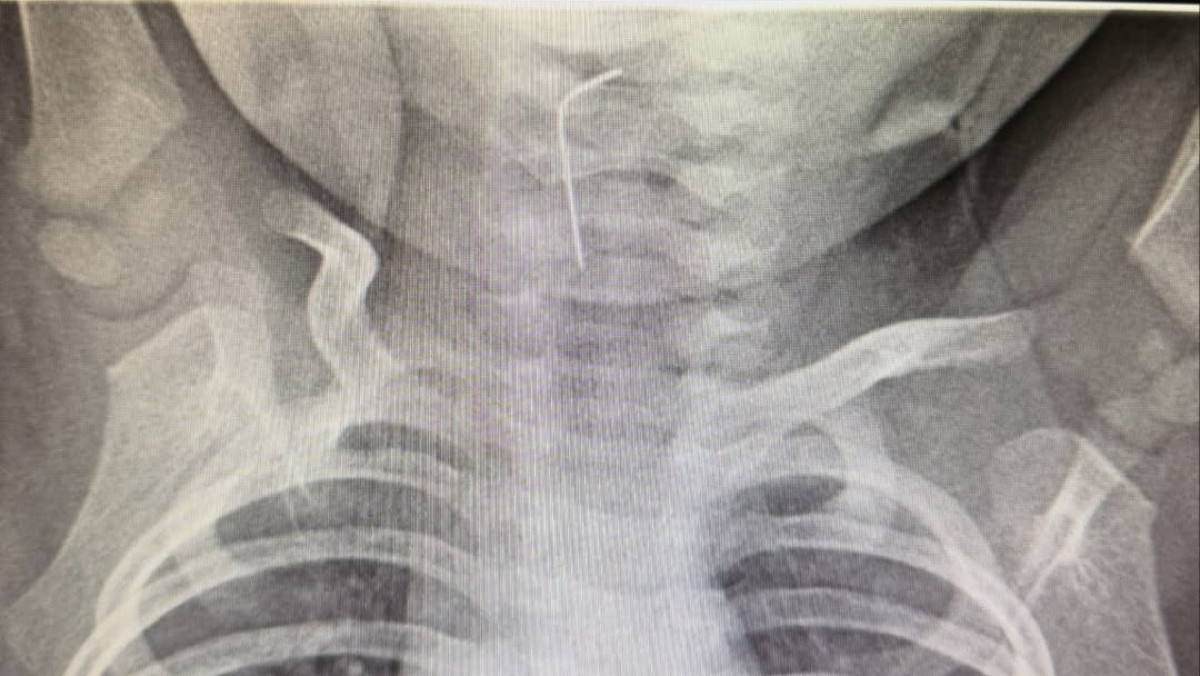

Фото: Департамент здравоохранения Туркестанской области

В областную детскую больницу Туркестанской области экстренно доставили 9-месячного ребёнка бригадой скорой помощи, передает BAQ.kz.

Как выяснилось, малыш по неосторожности проглотил иглу. Врачи оперативно провели обследование: хирург Мухагали Темирбеков и эндоскопист Бабыр Ырыскулов с применением эндоскопического метода и рентгенологического исследования определили точное расположение инородного предмета и успешно извлекли иглу из пищевода, сообщили в пресс-службе акимата Туркестанской области.